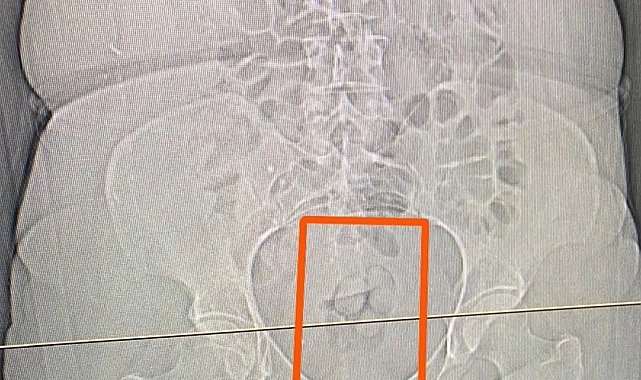

S.S. isimli şahısın şüpheli görülmesi üzerine çekilen tomografi neticesinde şahsın midesinde yabancı maddeler tespit edildi. Yapılan iç beden muayenesi sonucunda ise şahıstan 21,39 gram metamfetamin maddesi ele geçirildi.

Midesinden 21,39 gram uyuşturucu çıktı